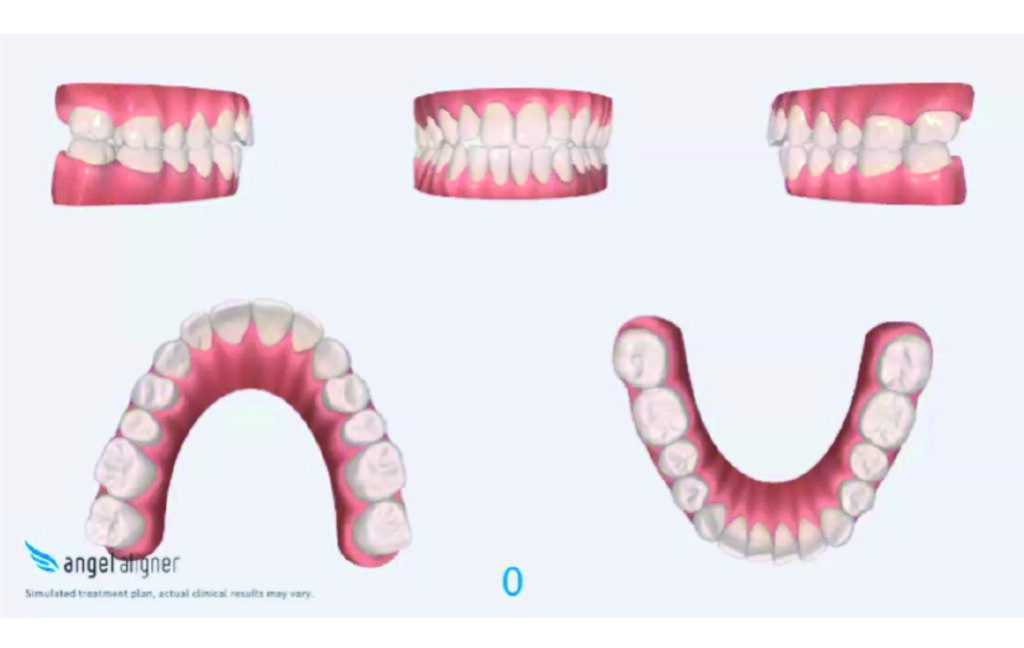

Number of aligners: 40

Malocclusion Class II on both sides due to mesial rotation of 16 26

Light mandibular asymmetry to the right with both midline deviation.

Severe attrition of posterior teeth, night bruxism. Open bite tendency.

Angle Class II 2mm on the right, Angle Class II 2mm on the left, light mandibular asymmetry to the right, lower central line 1mm to the right, upper central line 1,5mm to the left, 1mm overjet and overbite. Sagittal asymmetry of upper dental arch. Light crowding upper and lower frontal segments, severe attrition of posterior teeth, night bruxism. Normal sagittal position of both jaws, high angle case, steep mandibular ramus,excessive lower facial height, open bite tendency.

The case initially presented as a moderate Class II on the right and a Class II tendency on the left, with tapered dental arches and an anterior open bite extending to tooth 26 in segment II.

In segment I, the open bite reached up to the first premolar.

A 1.5 mm deviation of the upper dental midline to the patient’s left was noted, along with a slight mandibular midline shift to the right, likely due to asymmetrical mandibular growth observed in the facial structure. Severe mesial rotations of teeth 16 and 26 were evident in the initial records. As derotation of 16, 26, 17, and 27 progressed up to aligner 16, the premolars in segments I and II moved distally, resulting in a bilateral Class I relationship, as intended in the initial treatment plan.